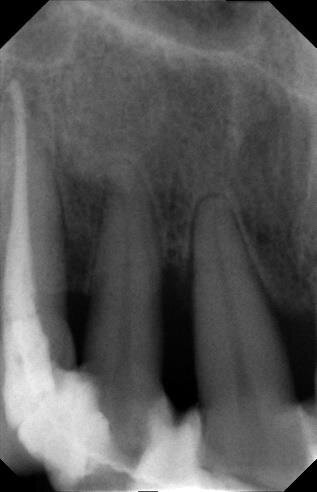

La paziente (che agirà in giudizio) 55 anni, fumatrice con scarso controllo dell’igiene domiciliare, in cura nel 1998 per parodontopatia cronica e compromissione dei quattro incisivi superiori (Figg. 1-5) per dodici anni, viene trattata con terapie chirurgiche e non2. Nel luglio 2010, dopo ben 12 anni di mantenimento di tali denti, si presenta all’osservazione dell’odontoiatra per la rottura dello splintaggio, riferendo di aver subito un accidentale trauma facciale.

Tutto ciò viene dettagliatamente spiegato sia verbalmente, sia descritto nel “Consenso informato” che la paziente sottoscrive dopo aver richiesto un secondo consulto presso un altro studio. Il trattamento estrusivo dei due incisivi laterali inizia nel gennaio 2011 (Figg. 7, 8). Al raggiungimento del risultato desiderato (Figg. 9, 10), si attendono 60 giorni di “stabilizzazione” dell’osso alveolare18 (Figg. 11, 12).

La fase chirurgica viene pianificata con la preparazione iniziale (igiene orale, controllo emato-chimico delle condizioni della paziente, prescrizione della profilassi/terapia antibiotica19-20 e della sospensione del fumo). Il 23 giugno 2011, vengono estratti i due incisivi laterali (Figg. 13, 14) e inseriti contestualmente due impianti Xive (Dentsply) di diametro 3,8 mm e lunghezza 15 mm (Figg. 15, 16), dimensioni ottimali per la successiva protesi (ponte di 4 elementi da 1.2 a 2.2 con 1.1 e 2.1, elementi “intermedi”).

Vengono inserite due viti di guarigione e riposizionato il provvisorio, debitamente adattato in corrispondenza dei due incisivi laterali. Alla seduta di controllo a una settimana dall’intervento implantare, la paziente confida, alle assistenti dello studio, di non aver assunto gli antibiotici prescritti né prima né dopo l’inserimento degli impianti e tantomeno di essersi astenuta o limitata dal fumo di sigarette! Alla seconda visita di controllo, dopo 30 giorni, la stessa presenta un pessimo stato di igiene orale e due ascessi vestibolarmente ai due impianti (1.2 e 2.2) (Figg. 17, 18).